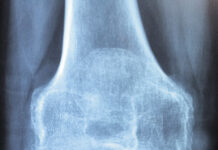

La dieta contro l’osteoporosi

Che cos’è l’osteoporosi?

La Commissione Intersocietaria per l’Osteoporosi definisce questa malattia “una patologia sistemica dello scheletro caratterizzata da una riduzione della massa ossea e da...